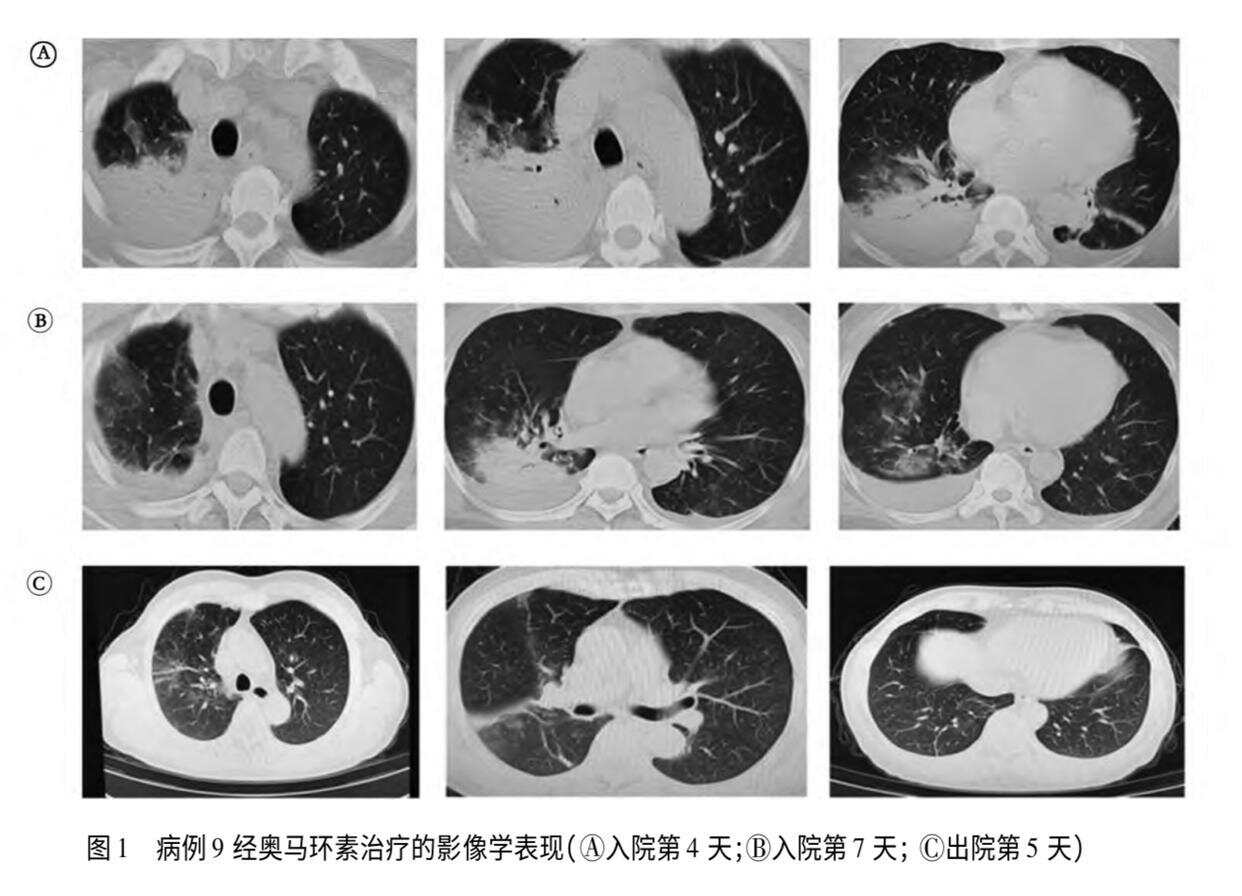

OCR:A B C 图1病例9经奥马环素治疗的影像学表现(A入院第4天;B入院第7天;C出院第5天)